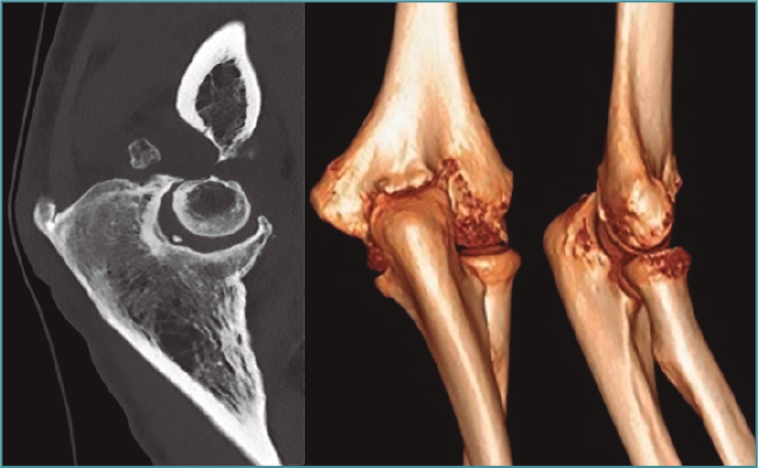

Las pruebas de imagen más útiles en este contexto son la radiografía simple (Figura 3) y la tomografía computarizada (TC) (Figuras 4 y 5), que evalúan la congruencia de las superficies articulares, la presencia de osteofitos u osificación ectópica, o alteraciones de la alineación ósea. Además, se evaluará la consolidación de fracturas previas, si es el caso, o la posible implicación del material de osteosíntesis en la falta de movilidad (si está correctamente situado, no tiene por qué interferir con la movilidad del codo)(6).

Figura 4. Artrosis de codo con formación osteofítica exuberante y fibrosis capsular, sin alteración del espacio o alineación articular, como ejemplo de rigidez extrínseca.

Figura 5. Reconstrucción sagital y tridimensional de una malunión de húmero distal, con alteración de la alineación de la superficie articular en extensión y malrotación interna, que condiciona una pérdida de flexión, como ejemplo de rigidez intrínseca.